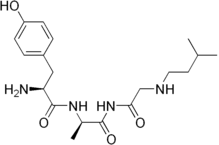

| Opioid peptides | Skeletal molecular images |

| Adrenorphin |  |

| Amidorphin |  |

| Casomorphin | |

| DADLE | |

| DAMGO |  |

| Dermorphin | |

| Endomorphin |  |

| Morphiceptin |  |

| Nociceptin |  |

| Octreotide |  |

| Opiorphin |  |

| TRIMU 5 |  |